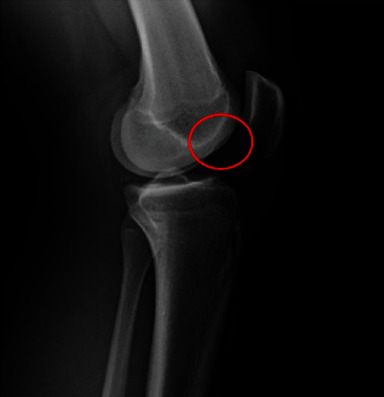

在急性前十字韧带(ACL)断裂的情况下,合并内侧和外侧后半月板根撕裂的情况极为罕见。以下病例报告显示,一名高中橄榄球运动员在训练中做旋转动作时膝盖非接触性受伤。患者是一名 17 岁的高中橄榄球防守后卫,受伤一周后到诊所就诊,主诉膝关节持续疼痛,伴有肿胀,活动范围(ROM)受限,并主诉膝关节不稳定。体格检查时发现患者膝关节前十字韧带松弛。磁共振成像(MRI)显示前交叉韧带中段完全撕裂,内侧半月板后角信号增强,外侧半月板局部无明显病变迹象。患者接受了前交叉韧带重建术(ACLR),术中发现内侧和外侧根部均有撕裂。手术采用标准的髌腱骨(BTB)自体移植前交叉韧带重建术,利用经胫骨牵引法对内侧和外侧根部进行联合修复。其临床意义在于,半月板根部撕裂伴有前交叉韧带撕裂很难在术前核磁共振成像中诊断出来,尤其是在侧方,因此在关节镜检查时仔细评估两个半月板根部至关重要。此外,为避免与前交叉韧带胫骨隧道合并,仔细创建经胫骨修复所需的半月板根修复隧道至关重要。

Combined medial and lateral posterior meniscal root tears in the setting of an acute anterior cruciate ligament (ACL) rupture are extremely rare. The following case report demonstrates a high school football player who sustained a noncontact knee injury while performing a spin move at practice. The patient is a 17-year-old high school football defensive end who was presented to the clinic 1 week following the injury complaining of persistent knee pain with associated swelling, limited range of motion (ROM), and complaint of instability. During physical examination, the patient was found to have anterior cruciate laxity. Magnetic resonance imaging (MRI) demonstrated a complete midsubstance tear of the ACL and increased signal within the posterior horn of the medial meniscus with no obvious signs of pathology localized to the lateral meniscus. ACL reconstruction (ACLR) was performed and intraoperatively, both medial and lateral root tears were found. A standard bone patellar-tendon bone (BTB) autograft ACLR was performed with combined medial and lateral root repair utilizing a transtibial pull-out method for both. The clinical importance is root tears with associated ACL tears can be hard to diagnose on preoperative MRI, especially laterally, so careful assessment of both meniscal roots at the time of arthroscopy is critical. Furthermore, careful creation of the needed root repair tunnels for transtibial repair is critical to avoid coalescence with the ACL tibial tunnel.